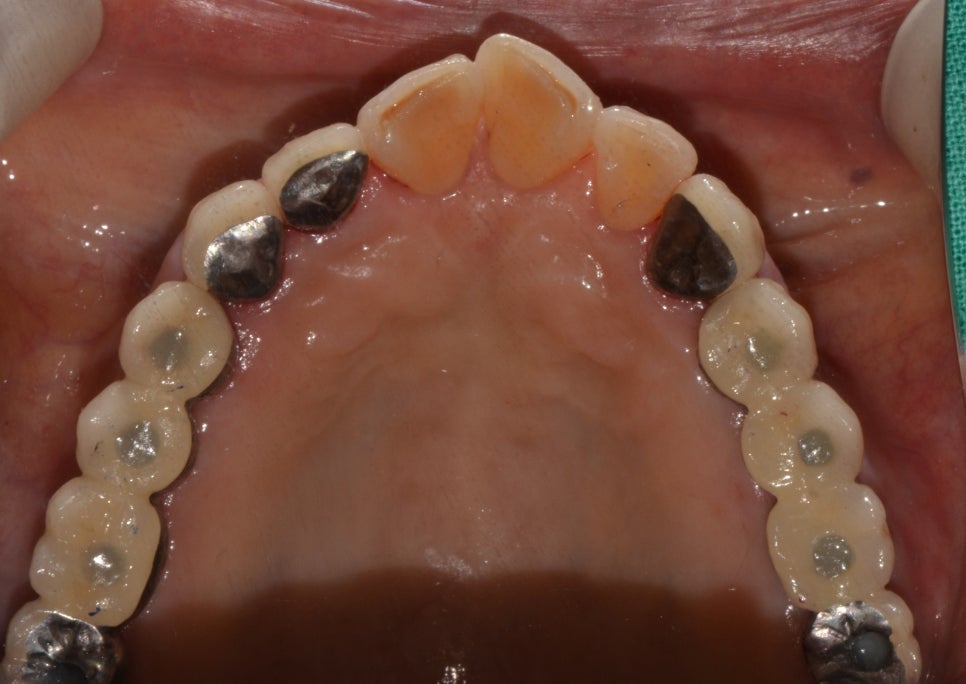

치료 후

2020년 1월 15일

치료 진행

치료 진행을 위해 정밀하게 구강 상태를 확인해 보니 상악 좌우 구치부 소실 및 골소실이 확인되어 좌우 임플란트 8개 식립 후 진행해 주었고 보철치료를 끝으로 치료를 마무리 하였습니다. 틀니 사용 시 불편함이 해소가 되고 위와 아래의 맞물림 또한 고려하면서 시술이 이뤄졌기 때문에 씹는 힘도 강해진 것 같다고 이제는 밥도 편하게 먹을 수 있을 것 같다고 만족해 주셨죠.